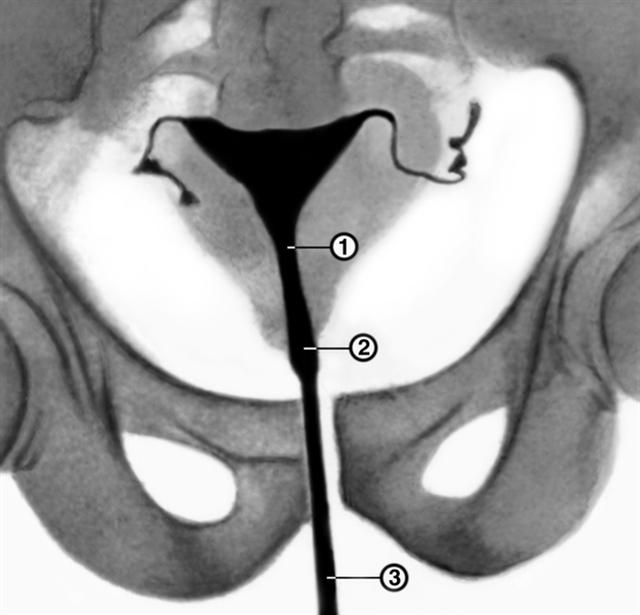

Рис. 1а). Гистерограмма в норме: 1 — перешеек матки, 2 — канал шейки матки, 3 — катетер, через который введено рентгеноконтрастное вещество.